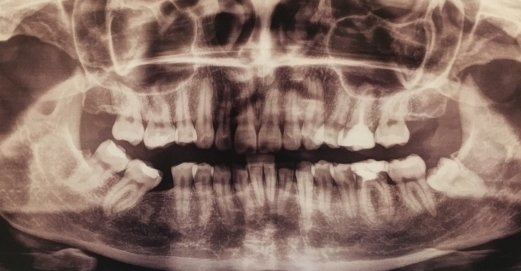

Летом удалили зуб, крайний нижний (не мудрости, а следующий). Десна в том месте зажила.

Пару дней назад вскочил на десне, где был зуб, волдырь или «пузырёк» красный и твёрдый, не болит, никак себя не проявляет, но как-то некомфортно с ним. До этого ещё болел соседний зуб под пломбой, но потом прошло. Может это как-то связано.

Полоскания тут не помогут, необходимо хирургическое вмешательство. Происхождение воспаления сказать сложно, возможно причина — седьмой зуб или оставленный корешок восьмого, что повлекло воспаление.